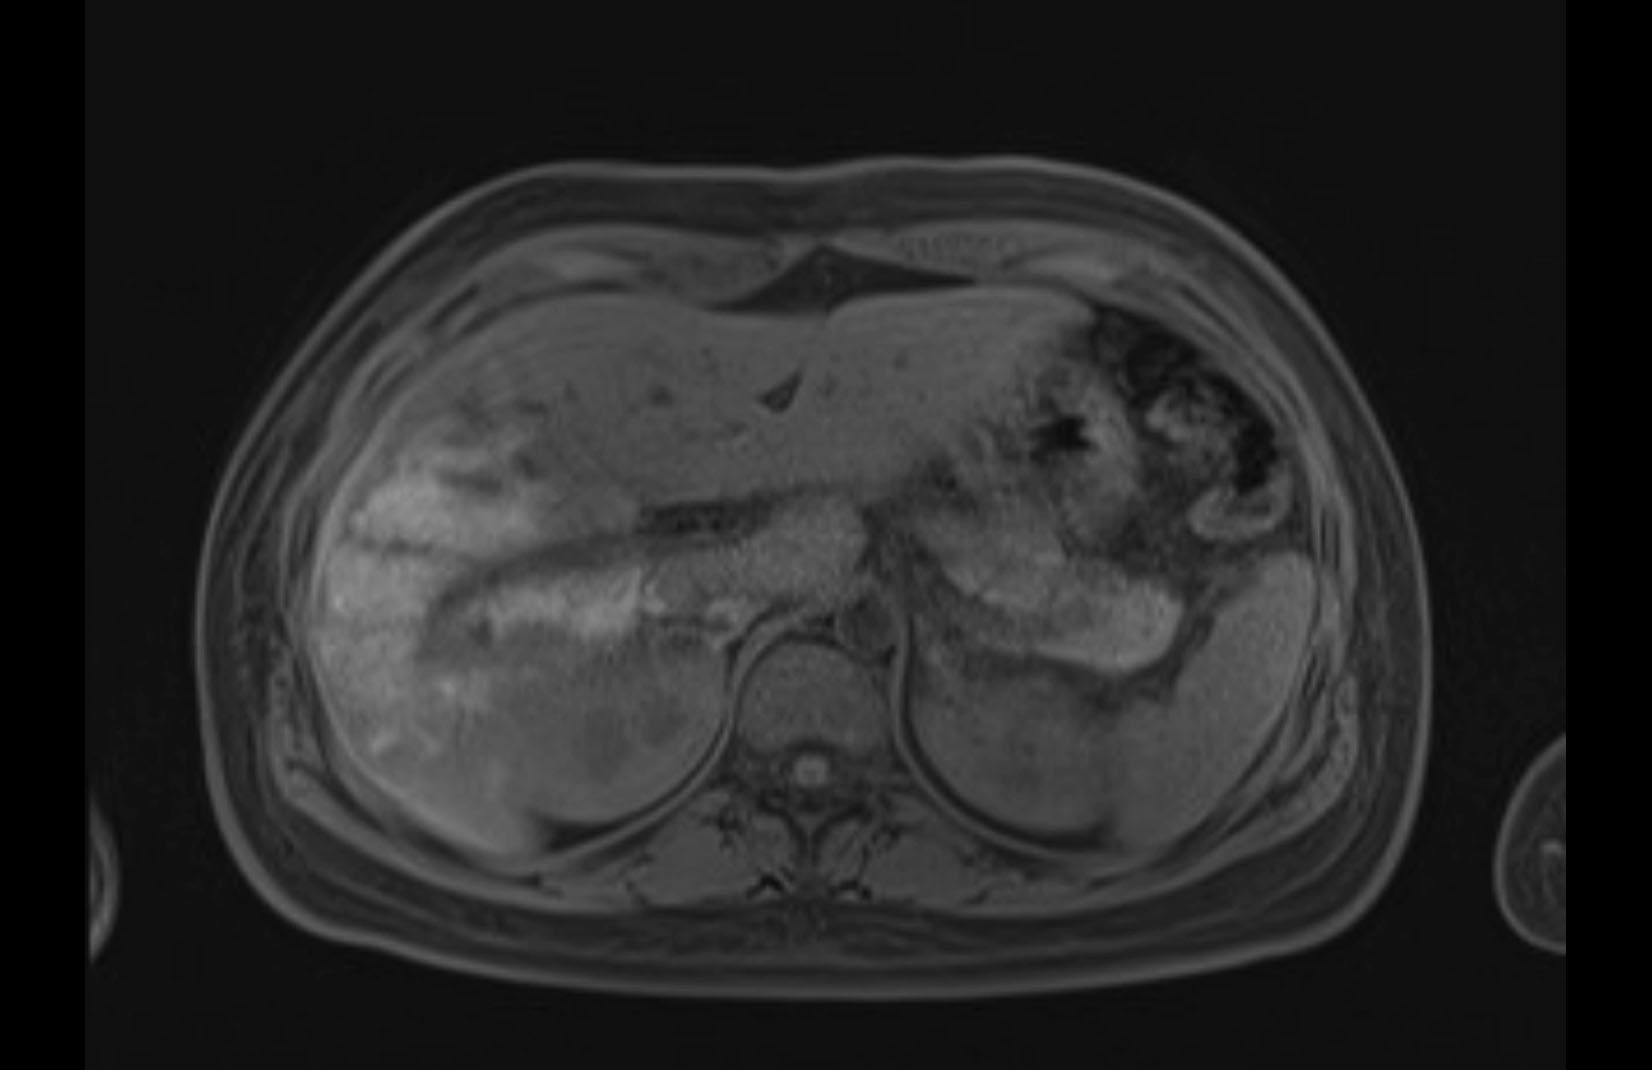

MRI T1

MRI T2